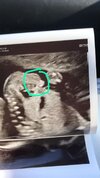

Moje usg połówkowe, całkiem pokaźna ta mosznaZ tymi jądrami to chyba gruba przesada. Chłopcom jądra schodzą do moszny bliżej końca ciąży.

SuperMoje usg połówkowe, całkiem pokaźna ta moszna![]()